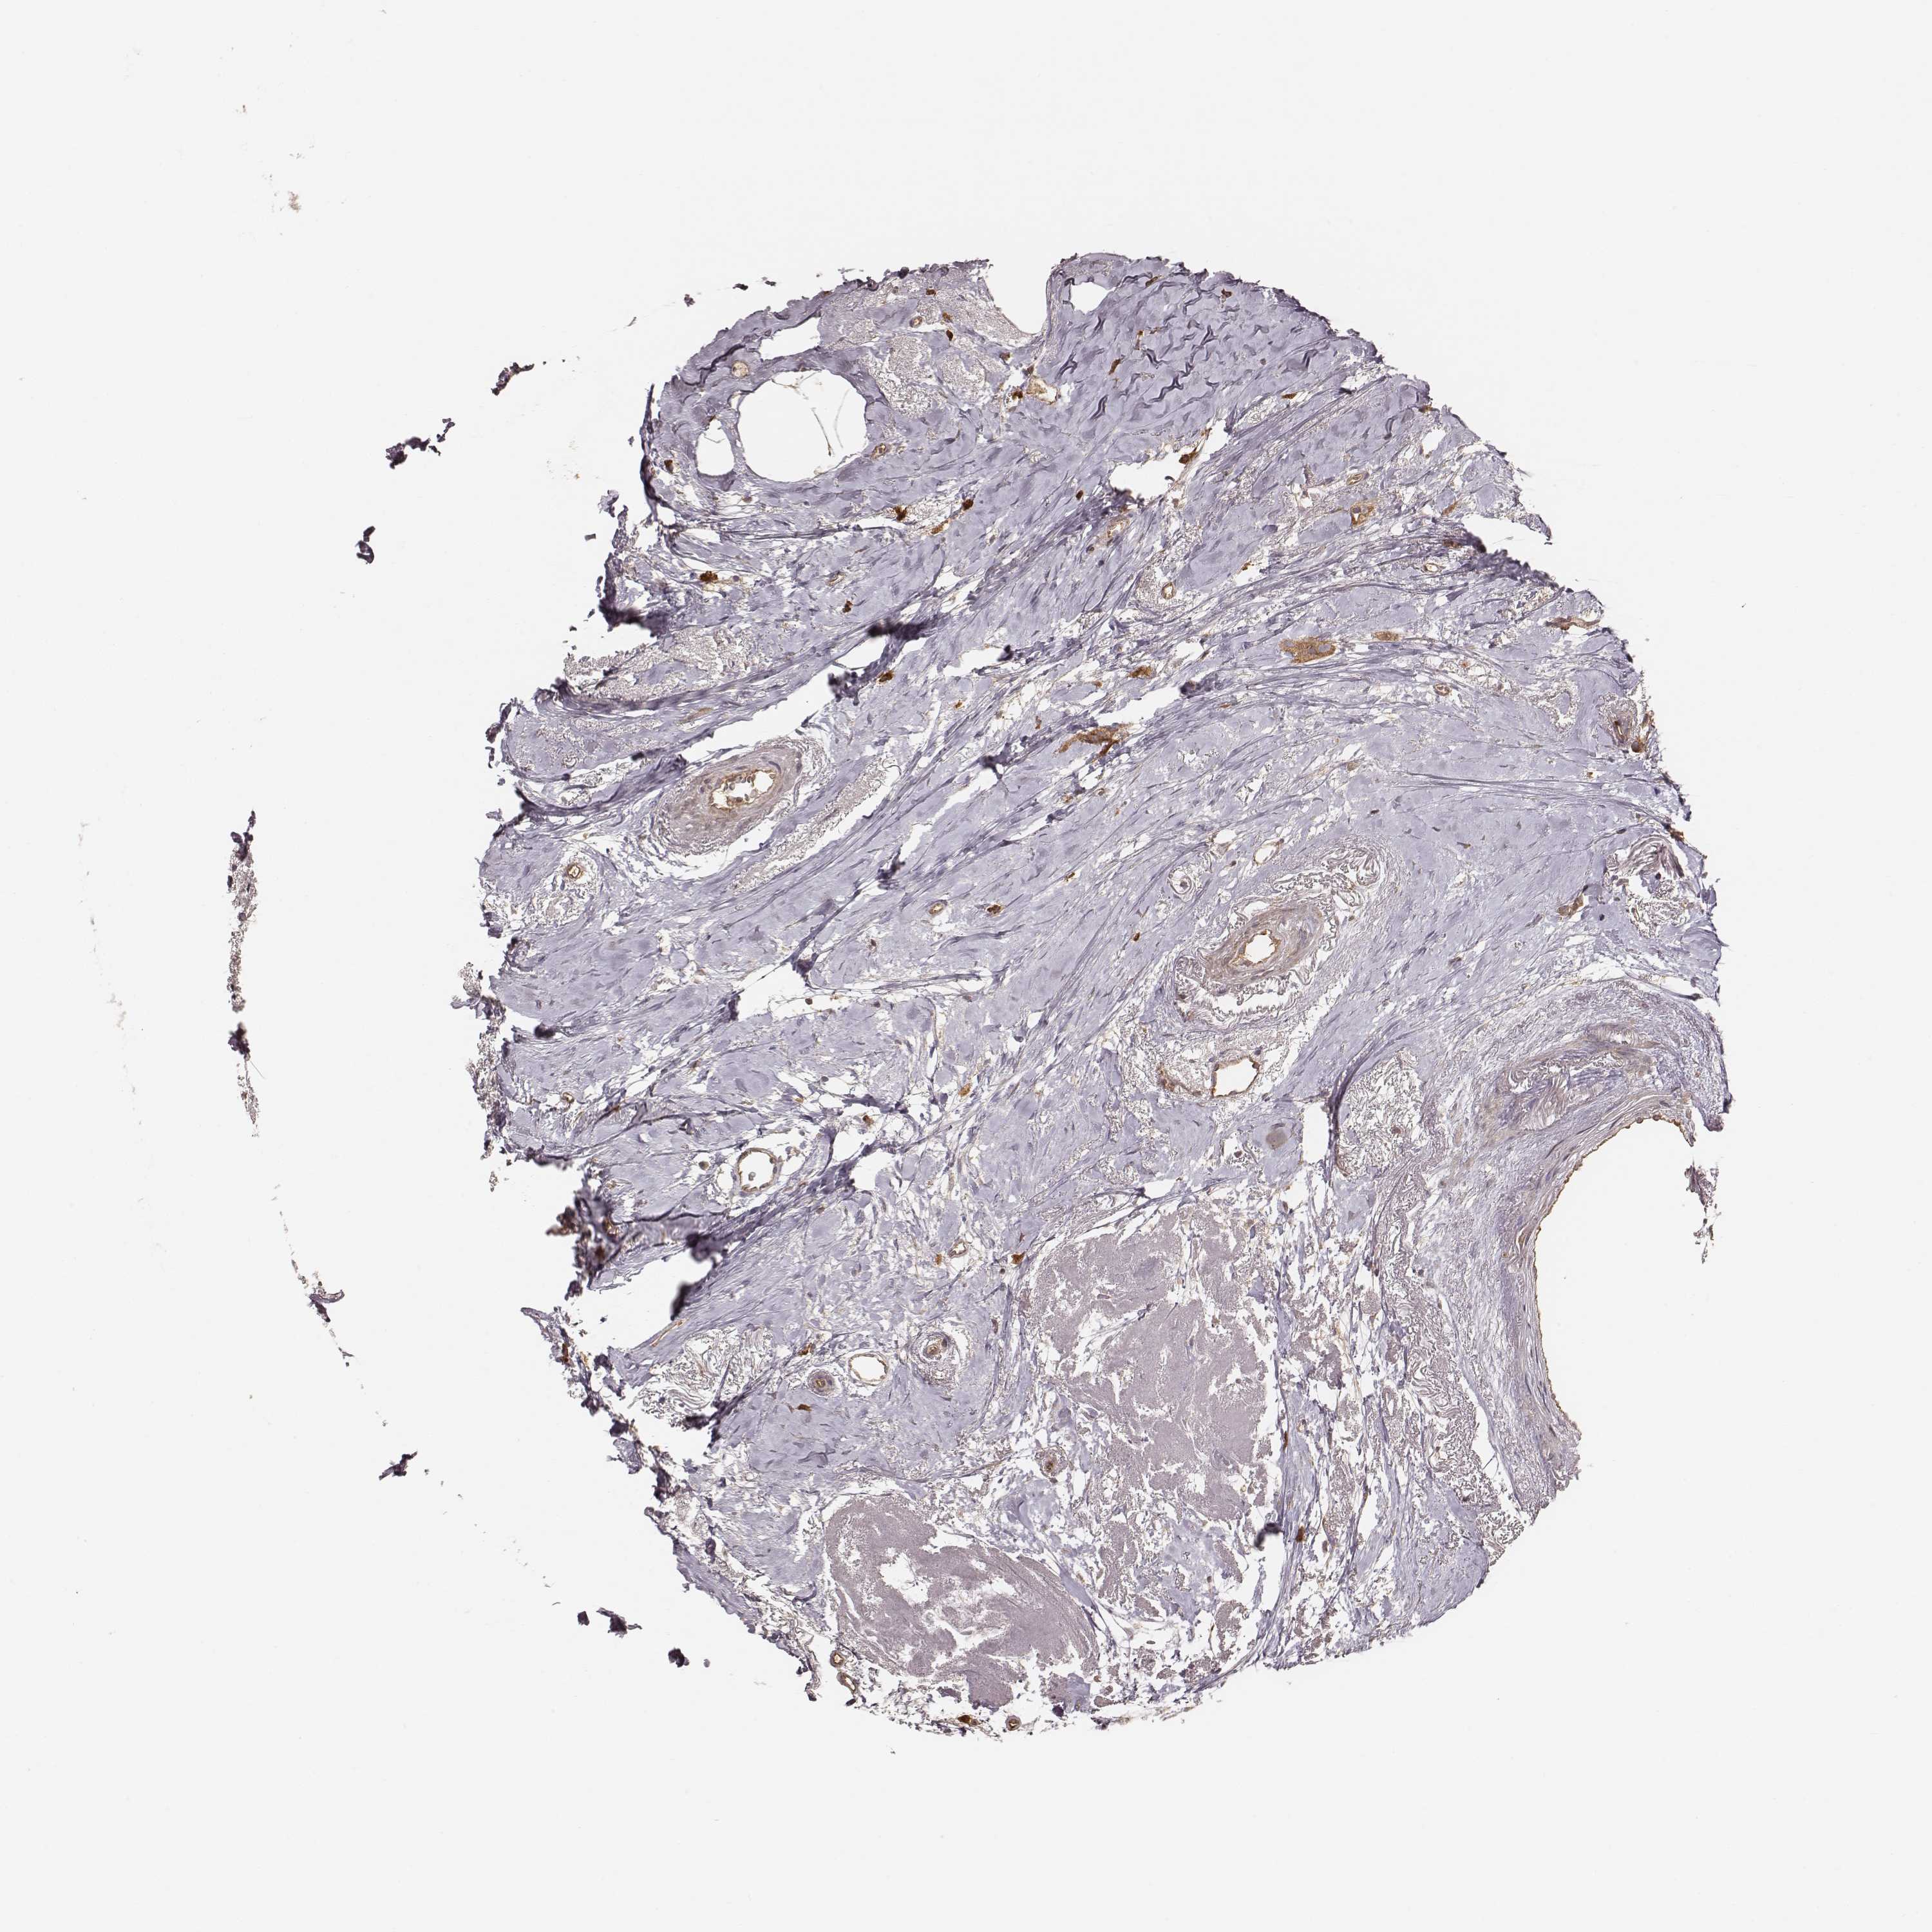

CANCER BREAST CANCER Show tissue menu

BRCA TCGA BRCA VALIDATION PROTEIN EXPRESSION